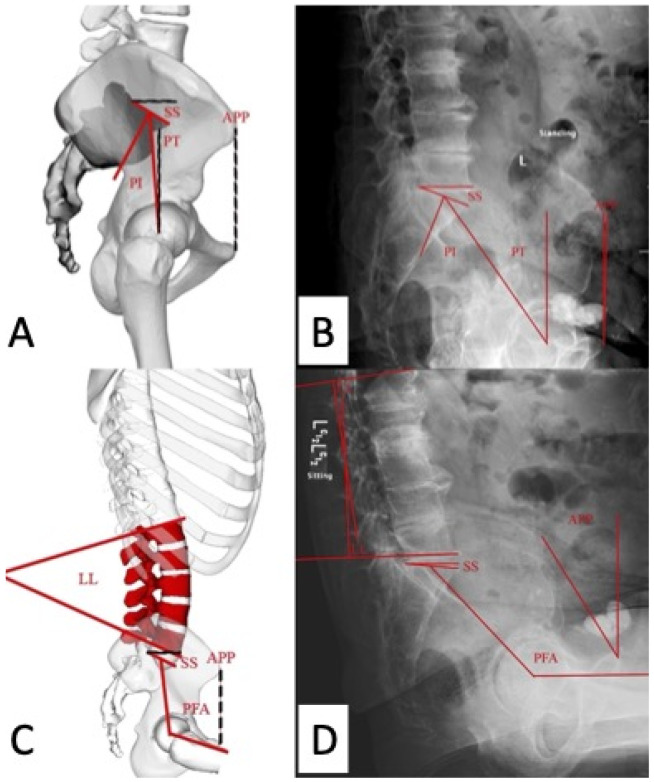

Total hip arthroplasty (THA) is an effective treatment for osteoarthritis, and the popularity of the direct anterior approach has increased due to more rapid recovery and increased stability. Instability, commonly caused by component malposition, remains a significant concern. The dynamic relationship between the pelvis and lumbar spine, deemed spinopelvic motion, is considered an important factor in stability. Various parameters are used in evaluating spinopelvic motion. Understanding spinopelvic motion is critical, and executing a precise plan for positioning the implant can be difficult with manual instrumentation. Robotic and/or navigation systems have been developed in the effort to enhance THA outcomes and for implementing spinopelvic parameters. These systems can be classified into three categories: X-ray/fluoroscopy-based, imageless, and computed tomography (CT)-based. Each system has advantages and limitations. When using CT-based systems, preoperative CT scans are used to assist with preoperative planning and intraoperative execution, providing feedback on implant position and restoration of hip biomechanics within a functional safe zone developed according to each patient's specific spinopelvic parameters. Several studies have demonstrated the accuracy and reproducibility of robotic systems with regard to implant positioning and leg length discrepancy. Some studies have reported better radiographic and clinical outcomes with use of robotic-assisted THA. However, clinical outcomes comparable to those for manual THA have also been reported. Robotic systems offer advantages in terms of accuracy, precision, and potentially reduced rates of dislocation. Additional research, including conduct of randomized controlled trials, will be required in order to evaluate the long-term outcomes and cost-effectiveness of robotic-assisted THA.